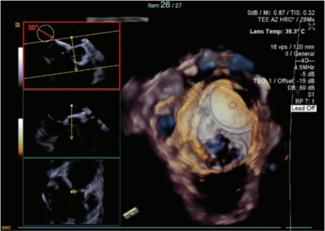

Nassir F. Marrouche, MD; Karim M. Al-Azizi, MD, FACC, FSCAI, FESC

Two leading voices in EP and interventional cardiology, Nassir Marrouche, MD, and Karim Al-Azizi, MD, discuss how technologies such as NUVISION NAV™ Ultrasound Catheter (Johnson & Johnson MedTech) 4D ICE are reshaping operator confidence.